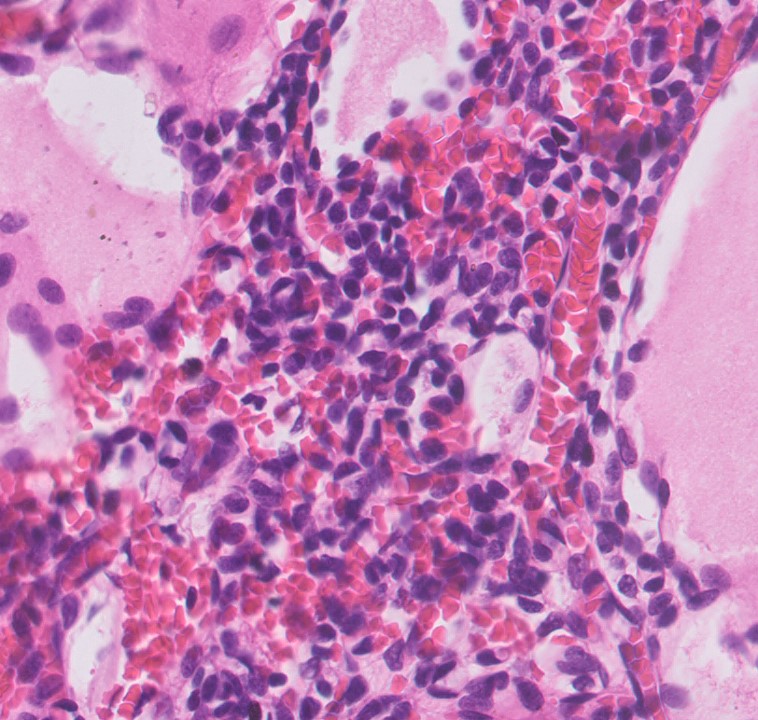

Microscopic (histologic) description

- Cysts lined with flat / cuboidal / hobnail cells (or are denuded)

- Epithelial elements consist mainly of mature and immature / abortive tubules and small papillae resembling immature glomeruli

- Key histological findings of the variably cellular septa include

- Nephroblastomatous epithelial elements

- Islands of undifferentiated blastema and differentiated mesenchymal elements (skeletal muscle and less often cartilage and fat) (J Urol 2010;183:1585)

- Focally, the septal elements may protrude into the cystic spaces in microscopic papillary folds

Microscopic (histologic) images

Contributed by Americo Brilhante, M.D. and Daniel Athanazio, M.D., Ph.D.